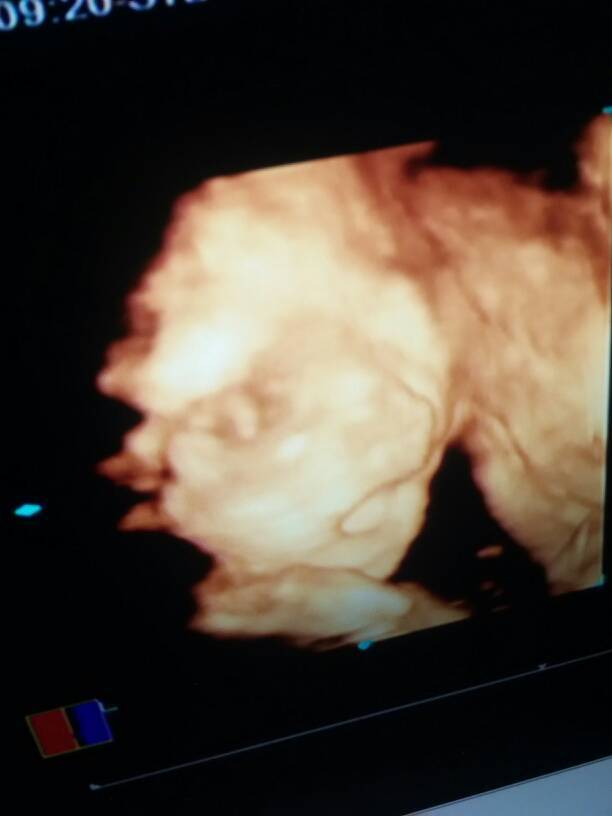

23周的三维彩超,朋友和医生说胎儿像我,能分辨出是儿子还是女儿吗? 23周的三维彩超,朋友和医生说胎儿像我,能分辨出是儿子还是女儿吗? 点击展开 亲爱的 2015-04-28 15:12 为您推荐: 其他回答 儿子像妈。 金宝521 2015-04-28 17:22 现在不明说,说像妈妈是女宝,像爸爸是男宝, 150*****484_IV8H 2015-04-28 16:07 是女宝宝。 150*****484_IV8H 2015-04-28 16:06 看不出来。 简💘爱💘 2015-04-28 15:52 你所提示的检查结果是看不出男女的,现在国家是禁止性别鉴定的,要顺其自然,男女一样 ,怀孕后要保持心情舒畅通,适当活动 。注意加强营养定期孕检。 hbwxsxl 2015-04-28 15:42 加载更多 相关问题 三维彩超,宝妈们医生们帮忙看看,正常吗?羊水会少吗?胎儿会偏小吗?六个月了 医生不告诉我胎儿性别,我要怎么才能知道自己怀的是个儿子还是女儿? 我朋友怀孕接近三个月,可医生说胎儿没成长,照出来只有七周大,请问像这种情况应该怎么做啊?必须是保不